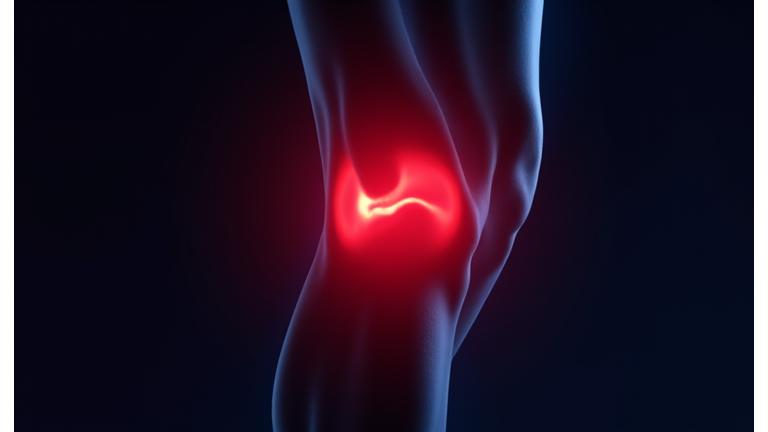

Natural Pain Relief Without Side Effects

Chronic pain can diminish your quality of life. Pyro Bloom offers evidence-based protocols utilizing red light and other alternative therapies to provide natural, lasting relief without the reliance on pharmaceuticals.

Targeting Arthritis & Joint Pain

Our protocols for arthritis combine red light therapy's anti-inflammatory effects with specific movement and dietary recommendations. Experience reduced stiffness and improved mobility within weeks.

- Typical Timeline: 4-6 weeks for significant relief.

- Modalities: Red Light Therapy, Gentle PEMF.

"After years of struggling with chronic knee pain from an old sports injury, red light therapy has been a game-changer. I'm back on the golf course, pain-free!"

— Arthur P., 62